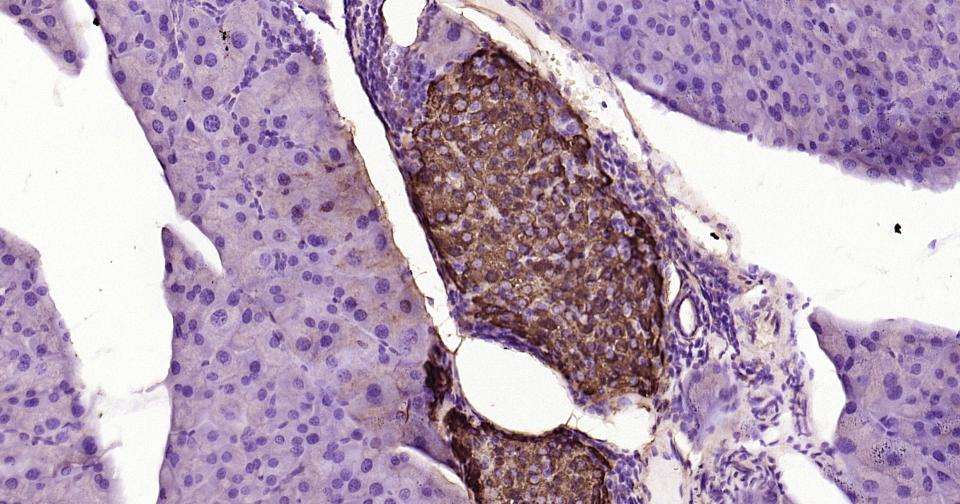

Paraformaldehyde-fixed, paraffin embedded Human Pancreas; Antigen retrieval by boiling in sodium citrate buffer (pH6.0) for 15 min; Antibody incubation with Notch1 Monoclonal Antibody, Unconjugated(bsm-60871R) at 1:200 overnight at 4°C, followed by conjugation to the bs-0295G-HRP and DAB (C-0010) staining.